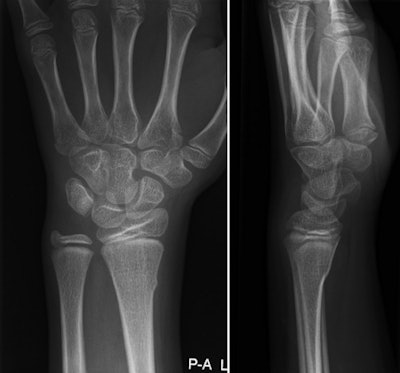

Using a clinical decision model developed by Dutch researchers for pediatric wrist trauma could cut unnecessary emergency x-ray imaging for the condition by 22% -- thereby reducing children's radiation exposure and healthcare costs, according to a study published online in Pediatric Radiology.

Wrist trauma is one of the most common reasons for children's visits to the emergency department, and over the past four decades, the number of distal forearm fractures, the most common type of injury following wrist trauma, has increased, wrote the group led by Dr. Annelie Slaar of the University of Amsterdam.

The rise in incidence has sparked a surge in cost -- to the tune of more than $2 billion per year in the U.S. -- in part because more x-rays are being performed to diagnose the injury. But no guidelines exist to help emergency physicians determine when x-ray imaging of wrist trauma is appropriate, and in a previous study, Slaar and colleagues found that only 51% of x-rays acquired for this reason actually showed a fracture (Pediatr Radiol, August 23, 2015).